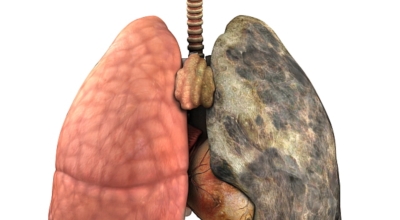

폐에 발생된 악성 종양을 말하며 오랜 기간 흡연해온 남성들에서 발병률이 높고 최근 들어 가지가지 환경적인 요인의 영향과 간접흡연으로 흡연하지 않는 여성에서도 많이 발생하고 있어요. 증상을 느껴 병원을 찾았을 때는 수술하기 늦은 경우가 많아 사망하는 비율이 매우 높은 암입니다. 폐 자체에서 생기거나 다른 장기에서 발생된 암이 폐로 전이되어 나타나기도 하고 특별한 초기 증상이 없는 경우가 많다고 하며 암이 진행된 후에도 일반적인 감기 증상인 기침과 가래 외의 특이 증상이 나타나지않아 증상만으로는 진단이 쉽지 않아요.

폐암의 공통 위험요소로 손꼽히는 까닭으로 흡연이 있어요. 흡연자는 비흡연자에 비교해 십몇 배는 더 폐암 발병확률이 높다고 하며 어느정도 기간 동안 흡연했는지에 따라 폐암 발생확률은 더욱더 더 높아져요. 흡연자라고 해도 금연을 하게 되면 폐암 발병확률이 가파르게 감소한다고 하니 폐암이 걱정되신다면 가장 먼저 금연은 필수입니다.